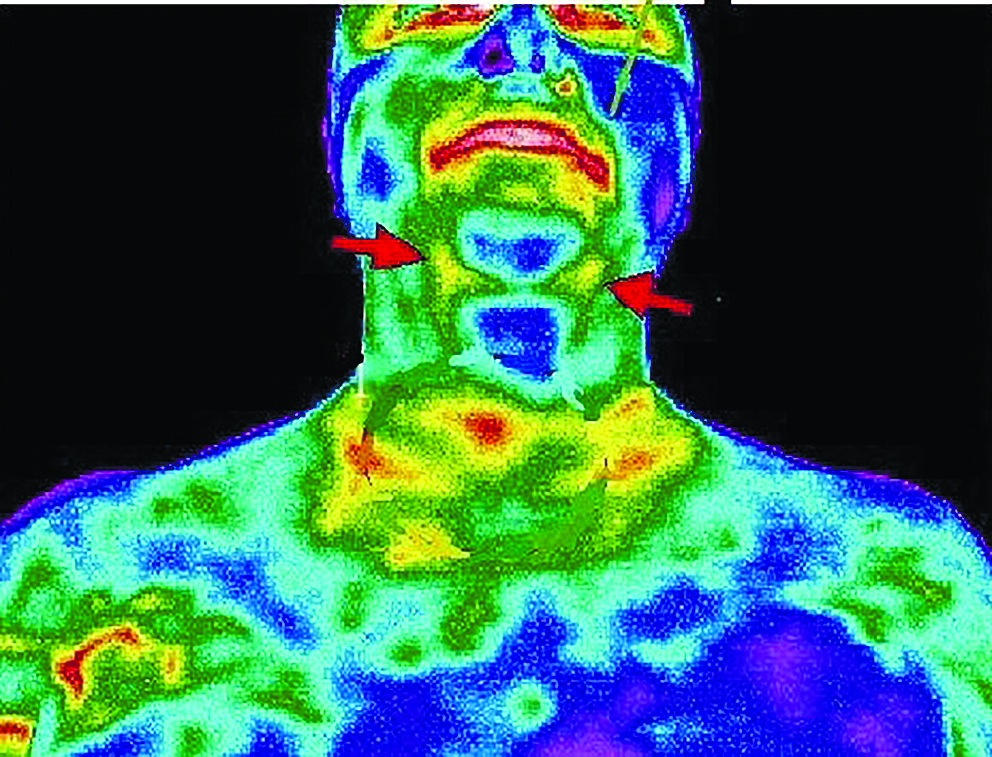

Большинство патологических процессов демонстрируют «форму повышенной жары», а некоторые неврологические процессы показывают чрезмерный холод или переохлаждение

- заболевания щитовидной железы;

- воспаления сонной артерии (риск инсульта);

Примеры диагностики